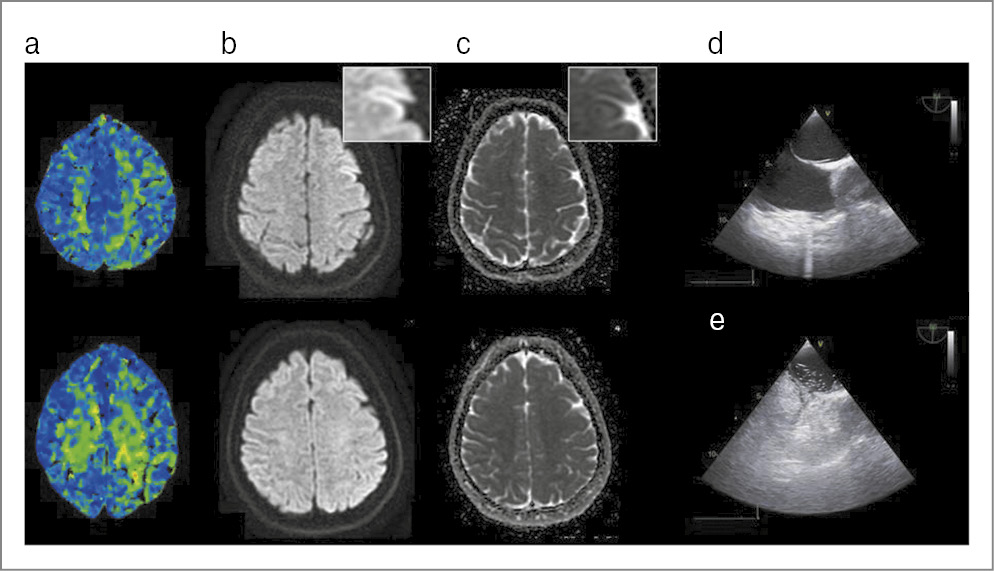

При поступлении отмечалось психомоторное возбуждение: пациент метался по кабинету, кричал, сопротивлялся медицинскому осмотру и диагностике. Двигательных нарушений не отмечено, речь и зрение оценить не представлялось возможным. На фоне медикаментозной седации проведена компьютерная томография (КТ) ГМ, зон патологической плотности не выявлено. Признаков окклюзии крупных и средних артерий, а также венозного тромбоза по данным КТ-ангиографии не выявлено. По данным КТ-перфузии показатели кровенаполнения повышены (гиперперфузия) в области верхних отделов мозжечка и медиобазальных отделов височных долей (рис. 1).

Рис. 1. Клинический случай №1: a – КТ-перфузия; b – МРТ (описание в тексте).

Пациент госпитализирован в отделение реанимации, выполнена люмбальная пункция. Получен анализ ликвора: глюкоза – 3,7 ммоль/л, цитоз – 3 кл/мкл, белок – 0,48 г/л. Продолжена медикаментозная седация. На следующее утро психомотороное возбуждение регрессировало, однако пациент жаловался на снижение зрения по типу нечеткости. В 11:00 выполнена МРТ ГМ (см. рис. 1), на которой отмечено повышение МР-сигнала на изотропных картах (b-1000), без изменения интенсивности на ИКД-картах (ИКД – измеряемый коэффициент диффузии) с повышением МР-сигнала на Т2 FLAIR от кортикальных отделов правых лобной, височной и островковой долей. В течение дня зрение полностью восстановилось. Пациент выписан через 5 дней в удовлетворительном состоянии. Провести повторную МРТ не удалось из-за клаустрофобии.

Несмотря на то что первый пациент доставлен в стационар с подозрением на острое нарушение мозгового кровообращения, инсульт удалось быстро исключить путем проведения КТ-ангиографии (отсутствие окклюзии крупной артерии) и КТ-перфузии (отсутствие зон, типичных для ишемии мозга). В силу особенностей клинической картины (ГБ и психомоторное возбуждение) дифференциальный ряд включал КТ-негативный случай субарахноидального кровоизлияния, энцефалит (в первую очередь герпетический) [17], синдром обратимой церебральной вазоконстрикции [18] и синдром транзиторной ГБ с неврологическим дефицитом и лимфоцитозом в цереброспинальной жидкости (HaNDL) [19]. Опровергнуть данные заболевания позволили нормальный анализ ликвора, монофазное течение заболевания с отсутствием рецидивов ГБ и результат контрольной МРТ ГМ (отсутствие патологических зон, характерных для энцефалита, и признака гиперинтенсивных на FLAIR артерий, характерного для вазоконстрикции). С учетом наличия в анамнезе у пациента МА развившееся состояние расценено как приступ мигрени со спутанностью (acute confusional migraine) – вариант заболевания, проявляющийся спутанностью сознания, ажитацией, дезориентацией, изменением психического статуса, нарушением речи и памяти. Мигрень со спутанностью характерна для детей и подростков, однако в 17% случаев развивается у лиц 18 лет и старше. В 1/3 случаев у пациентов наблюдаются зрительные нарушения. Считается, что изменение сознания может выступать следствием корковой распространяющейся деполяризации [20]. Примечательно, что дебют в виде психомоторного возбуждения описан также при гемиплегической мигрени [21]. В литературе обнаружено лишь одно описание КТ-перфузии у пациента с данным состоянием: наблюдалось снижение кровотока в левой височной доле [22]. В представленном нами случае можно предположить наличие гиперперфузии в лимбических зонах ГМ, что соотносится с клинической картиной заболевания. Известно, что во время приступа мигрени гиперперфузия приходит на смену первоначальной гипоперфузии, соответствующей ауре [23]. В литературе имеется единичное описание обратимого отека коры ГМ по МРТ у пациентов с пролонгированной МА [9]. В представленном нами случае выявленные на контрольной МРТ изменения соответствовали сохраняющимся на тот момент зрительным расстройствам, что подтверждает патогенетическую значимость обнаруженного феномена. К сожалению, наличие у пациента клаустрофобии не позволило выполнить повторную МРТ.